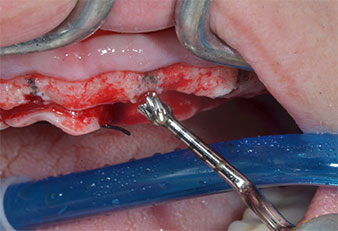

Ein flammenförmiges, diamantiertes piezochirurgisches Instrument (Piezomed I1) wurde verwendet, um die Implantatpositionen zu markieren und die Pilotpräparationen durchzuführen (Abb. 3). Dabei wurde darauf geachtet, eine Auf- und Abbewegung mit reduzierter Leistung, voller Spülung und niedrigem Druck (unter 300 g) anzuwenden. Als Nächstes wurde ein Pilotinstrument (Piezomed I2A/I2P) zur initialen Erweiterung der Implantatlager auf einen Durchmesser von 2 mm verwendet (Abb. 4), gefolgt von einem 3-mm-Instrument (Abb. 5).

Abb. 4: Der nächste Schritt ist die initiale Erweiterung mit den Instrumenten Piezomed I2A/I2P, die in einer horizontalen Drehbewegung verwendet werden.

Bei dichtem Knochen sollte das gesamte Set, einschließlich der Zwischeninstrumente Piezomed Z25P und Z35P verwendet werden, um die Osteotomien vor dem nächsten Schritt zu erweitern.

Diese Instrumente sind auch für die Aufbereitung bei interner Sinusbodenaugmentation in der Nähe der Sinusmembran indiziert oder wenn weniger als 4 mm Restknochenhöhe verbleibt.

Im vorliegenden Fall wurden die Instrumente Z25P und Z35P wegen des relativ weichen posterioren Knochens nicht verwendet, der problemlos mit dem I3A/I3P bearbeitet werden konnte.